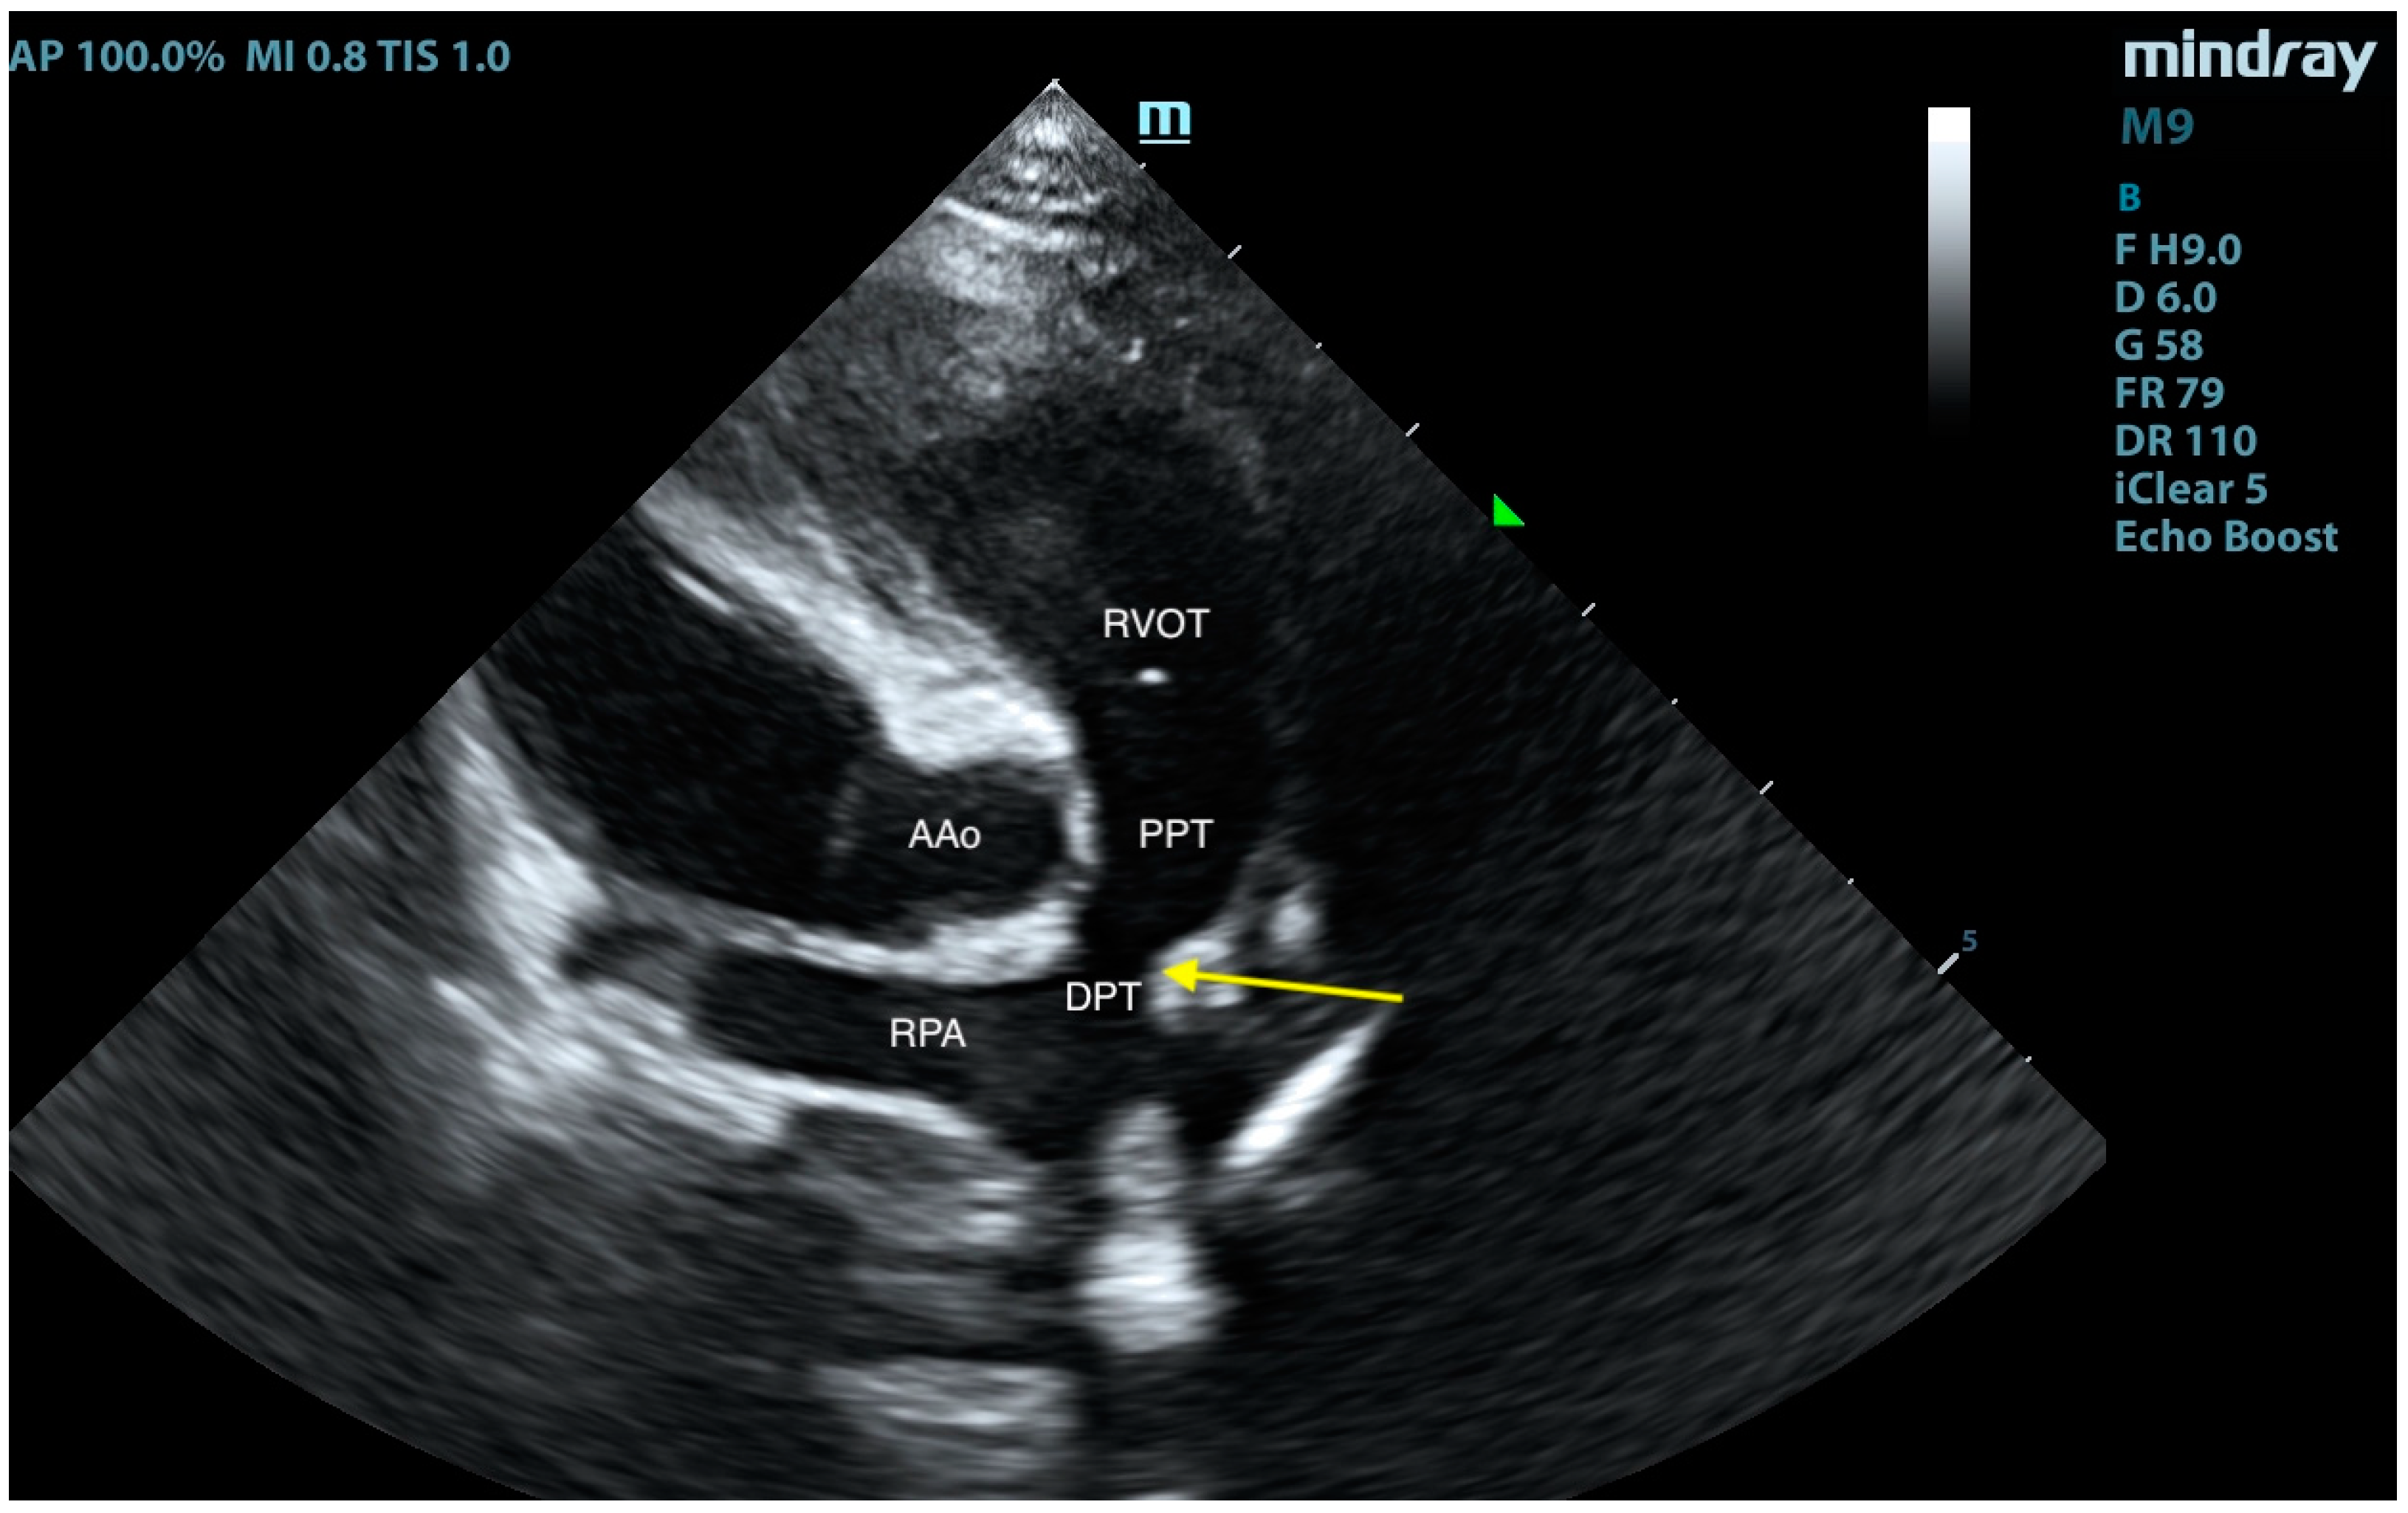

2. Case Presentation